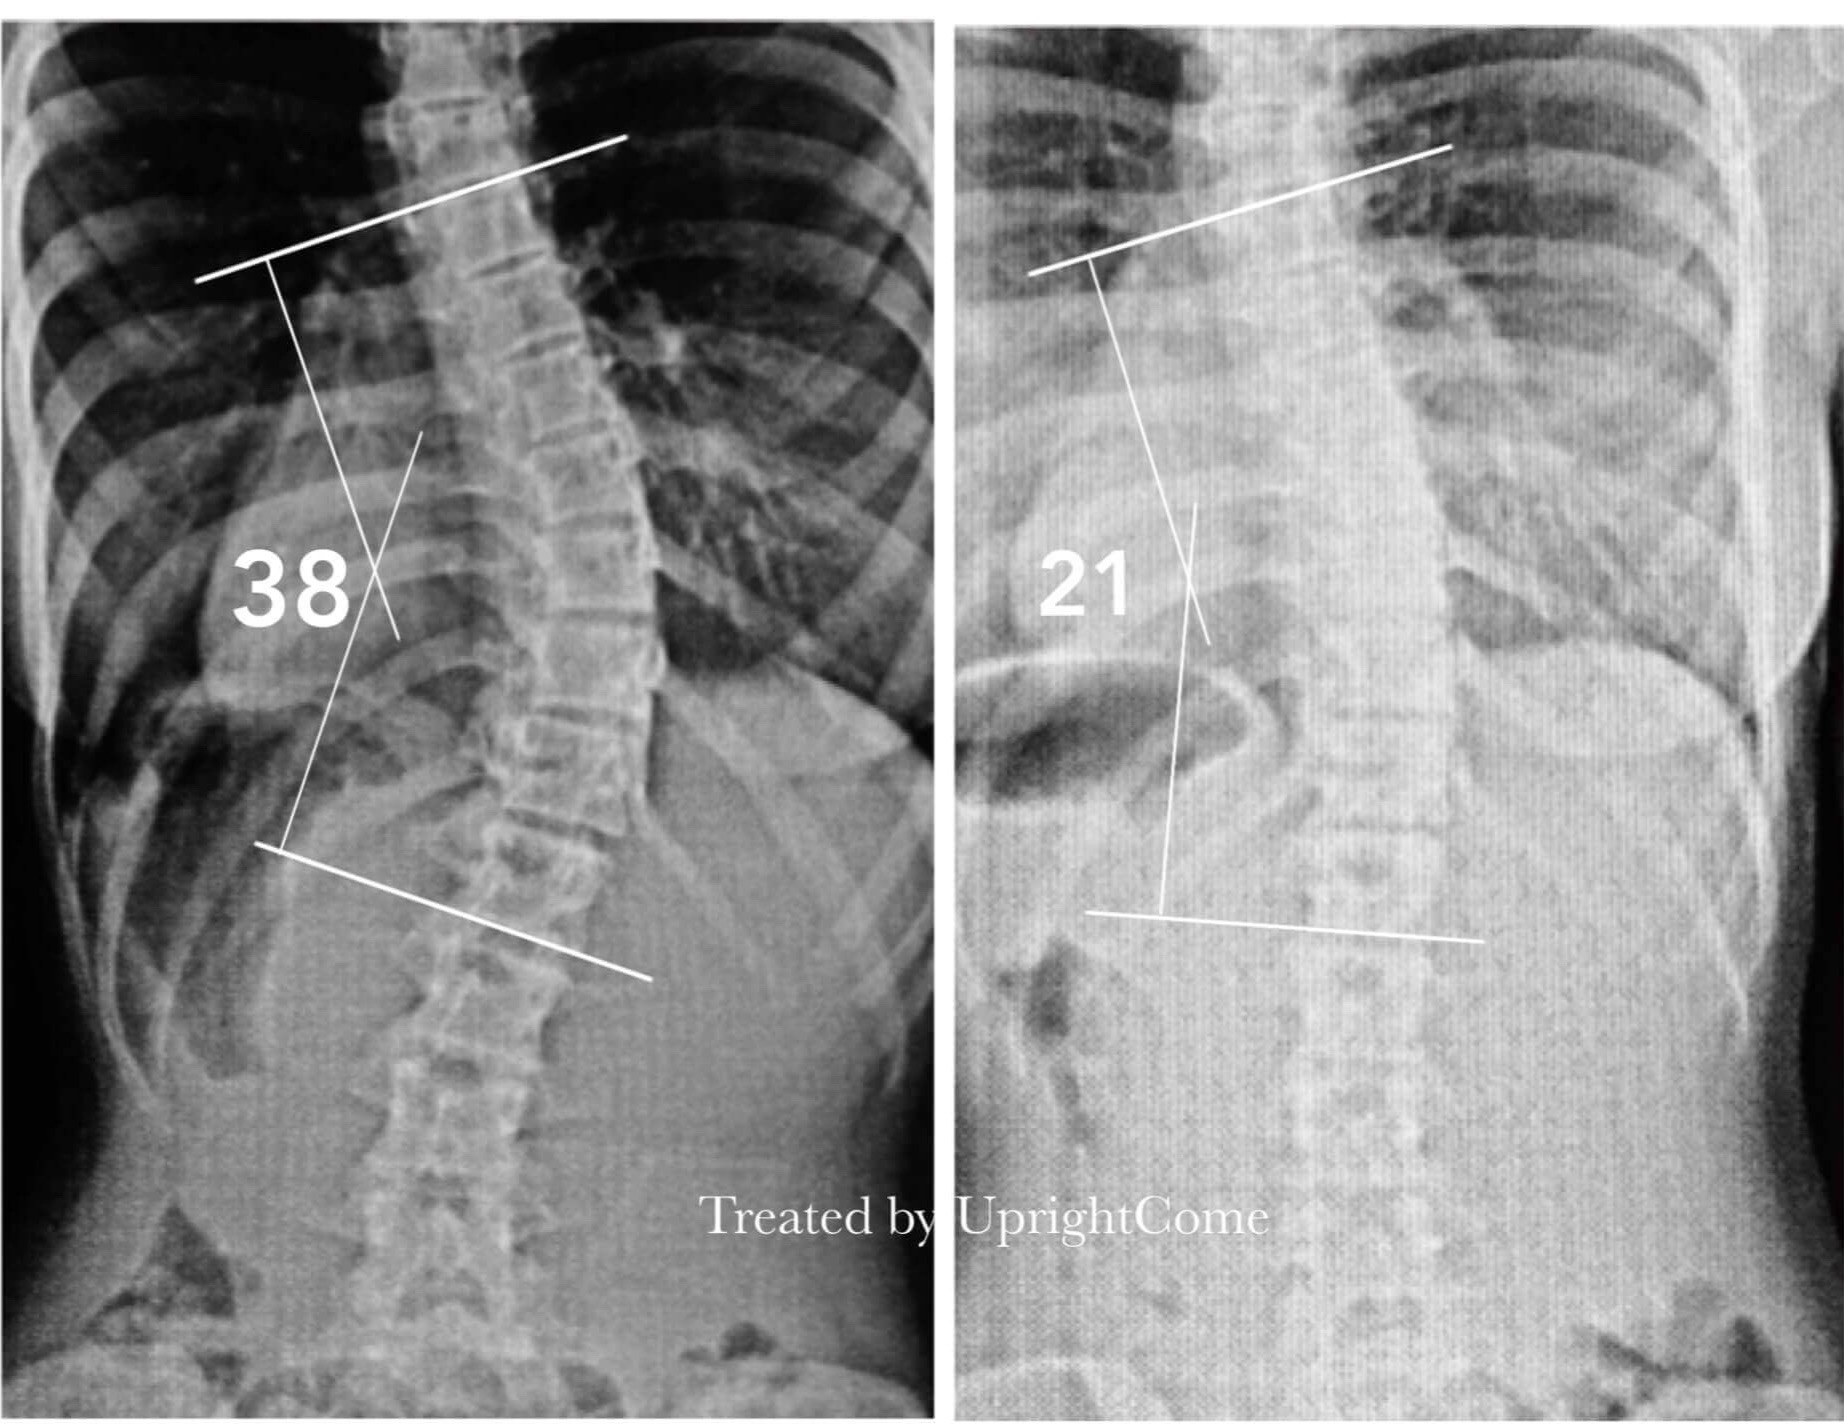

Case 14, 16 years old, 38° Cobb

![脊椎側彎患者經過側彎矯正治療後,胸椎側彎角度由38度減少到21度。]()